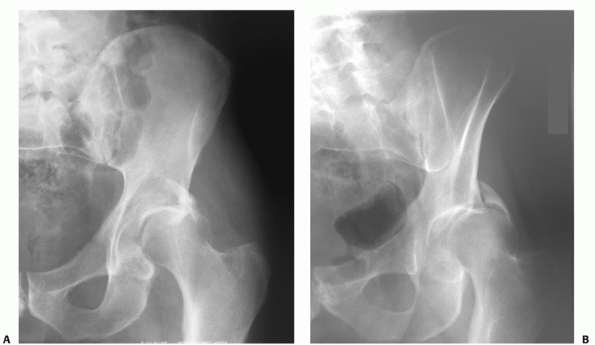

oblique view,17 and this view has been advocated for routine evaluation of all posterior fracture dislocations of the hip joint129 (Fig. 45-10).

FIGURE 45-10 Anteroposterior (A) and obturator oblique view (B) showing a dislocated hip with an associated posterior wall fracture. (Copyright Berton R. Moed, MD.)